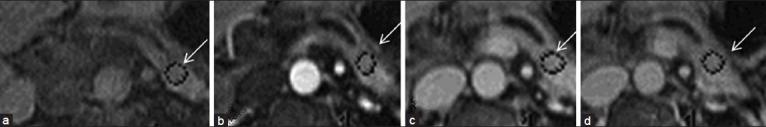

S-MRCP studies (n = 83) performed at Brigham and Women's Hospital between 1/2005 and 7/2005 were retrospectively reviewed. Among these, there were 13 patients (10 females, 3 males; mean age = 45 years, range = 18-74 years) who were evaluated with S-MRCP following pancreatojejunal anatomosis. Single-shot fast spin-echo T2-weighted thick slab dynamic MRCP images obtained before and every minute (for 10 min) after IV injection of secretin (2 mcg/kg body weight of SecreFloTM IV over 1 min) were reviewed retrospectively and independently by 3 readers. Image analysis included measurement of the main pancreatic duct (MPD) diameter and subjective assessment of the grade of visualization of the MPD remnant. The amount of jejunal fluid and visualization of the pancreatico-jejunal anatomosis pre-and post-secretin were also documented. Direct correlation with endoscopic retrograde cholangiopancreatography (ERCP) finding was available in six of the 13 cases.

The MPD diameter and MPD remnant visualization improved post-secretin for 1/3 readers. The number of pancreatico-jejunal anastomoses and the amount of jejunal fillings pre-and post-secretin was seen to improve significantly for 1 of the 3 readers. For Reader 1, the mean MPD diameter in the body of the pancreas, on the pre-and post-secretin image, was 3.2 ± 1.3 mm and 3.8 ± 1.9 mm, respectively. There was no statistical difference in the values pre- and post-secretin in the MPD diameter (P = 0.07), MPD visualization (P = 0.16) and the number of pancreatico-jejunal anastomoses seen (P = 0.125 5/13 pre- and 9/13 post-secretin). Statistical significance was seen in the amount of jejunal filling (P = 0.01) after secretin. For Reader 2, the MPD diameter pre-and post-secretin was 4 ± 2 and 3.9 ± 2.1 mm, respectively (P = 0.89). The MPD visualization (P = 0.19) and degree of jejunal filling (P = 0.7) did not improve significantly. There were 3/13 pancreatico-jejunostomy anastomoses seen pre- and 8/13 seen post-secretin (P = 0.06). The values for Reader 3 reached a statistical significance for the measurement of MPD (P = 0.032). In addition, MPD visualization (P = 0.038), the number of anastomoses seen (P = 0.016) and jejunal filling (P = 0.006) were also significantly improved.